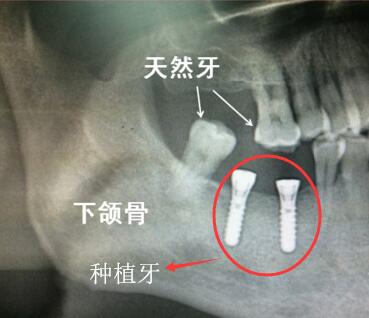

天然牙與(yu) 種植牙

烤瓷牙壞了怎麽(me) 修複看牙根情況。畢竟烤瓷牙使用的真牙牙根,而如果需要做種植牙的話,是要拔除真牙牙根,植入人工牙根的,而人工牙根哪有自己的牙根好。

為(wei) 什麽(me) 有的**烤瓷牙出現繃瓷等情況了,醫生會(hui) 建議繼續做烤瓷牙修複呢?因為(wei) 烤瓷牙是真牙牙根,而醫生對真牙很珍惜,但凡是真牙組織還能保留繼續使用的,就不會(hui) 輕言放棄。所以如果牙根還能繼續用,就聽醫生醫囑,繼續烤瓷牙修複吧。

如果烤瓷牙裏麵的基牙壞掉嚴(yan) 重,牙根也無法保留了,需要拔牙的話,則可以考慮去除烤瓷牙後,在牙齒缺失的位置做種植牙。

那麽(me) 烤瓷牙反正都會(hui) 壞掉,如果烤瓷牙後悔了不如直接拆掉烤瓷牙,拔除牙根,直接做種植牙!這是不少網友的想法,而實際上,醫生們(men) 通常不會(hui) 采取這樣的方法,因為(wei) 真牙和假牙沒法比,哪怕是和真牙很相似的種植牙,也隻是相似,而不是真牙!因此,建議大家也需要有這種盡量保護口內(nei) 真牙的意識,不要盲目做種植牙修複,否則適得其反。